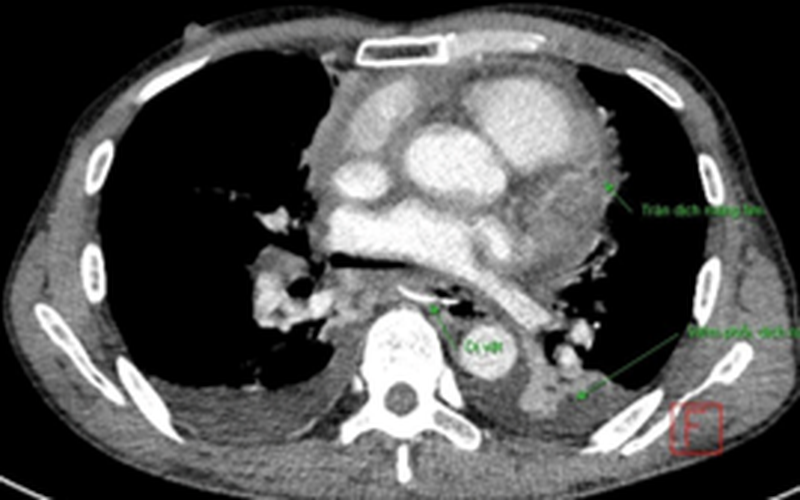

Tại Bệnh viện Bạch Mai, sau khi thăm khám lâm sàng và cận lâm sàng, các bác sĩ đánh giá đây là 1 trường hợp hóc xương cá gây biến chứng thủng thực quản, gây áp xe trung thất, tràn mủ màng tim.

Bệnh nhân đã được tiến hành thủ thuật dẫn lưu màng ngoài tim ra nhiều dịch mủ trắng, nhịn ăn, đặt sonde dạ dày; phối hợp điều trị kháng sinh. Tuy nhiên, bệnh nhân vẫn sốt cao, đau ngực khó thở nhiều. Nội soi thực quản dạ dày thấy tổn thương là xương cá gây thủng thực quản, chảy mủ vào lòng thực quản; nhưng không thể can thiệp gắp bỏ dị vật qua nội soi.

Bệnh nhân được phẫu thuật nội soi ngực phải xác định tổn thương là dị vật – xương cá (mang cá) đâm thủng thực quản, màng tim, gây áp xe trung thất và tràn mủ màng ngoài tim. Các bác sĩ đã làm sạch áp xe trung thất; lấy dị vật xương cá; mở màng tim; dẫn lưu màng phổi 2 bên, dẫn lưu màng tim; nội soi ổ bụng mở thông hỗng tràng để nuôi dưỡng.

Sau mổ, bệnh nhân được bơm rửa màng tim; phối hợp điều trị kháng sinh, nuôi dưỡng qua mở thông hỗng tràng. Sau 2 tuần, bệnh nhân được rút dẫn lưu màng phổi và dẫn lưu màng tim.